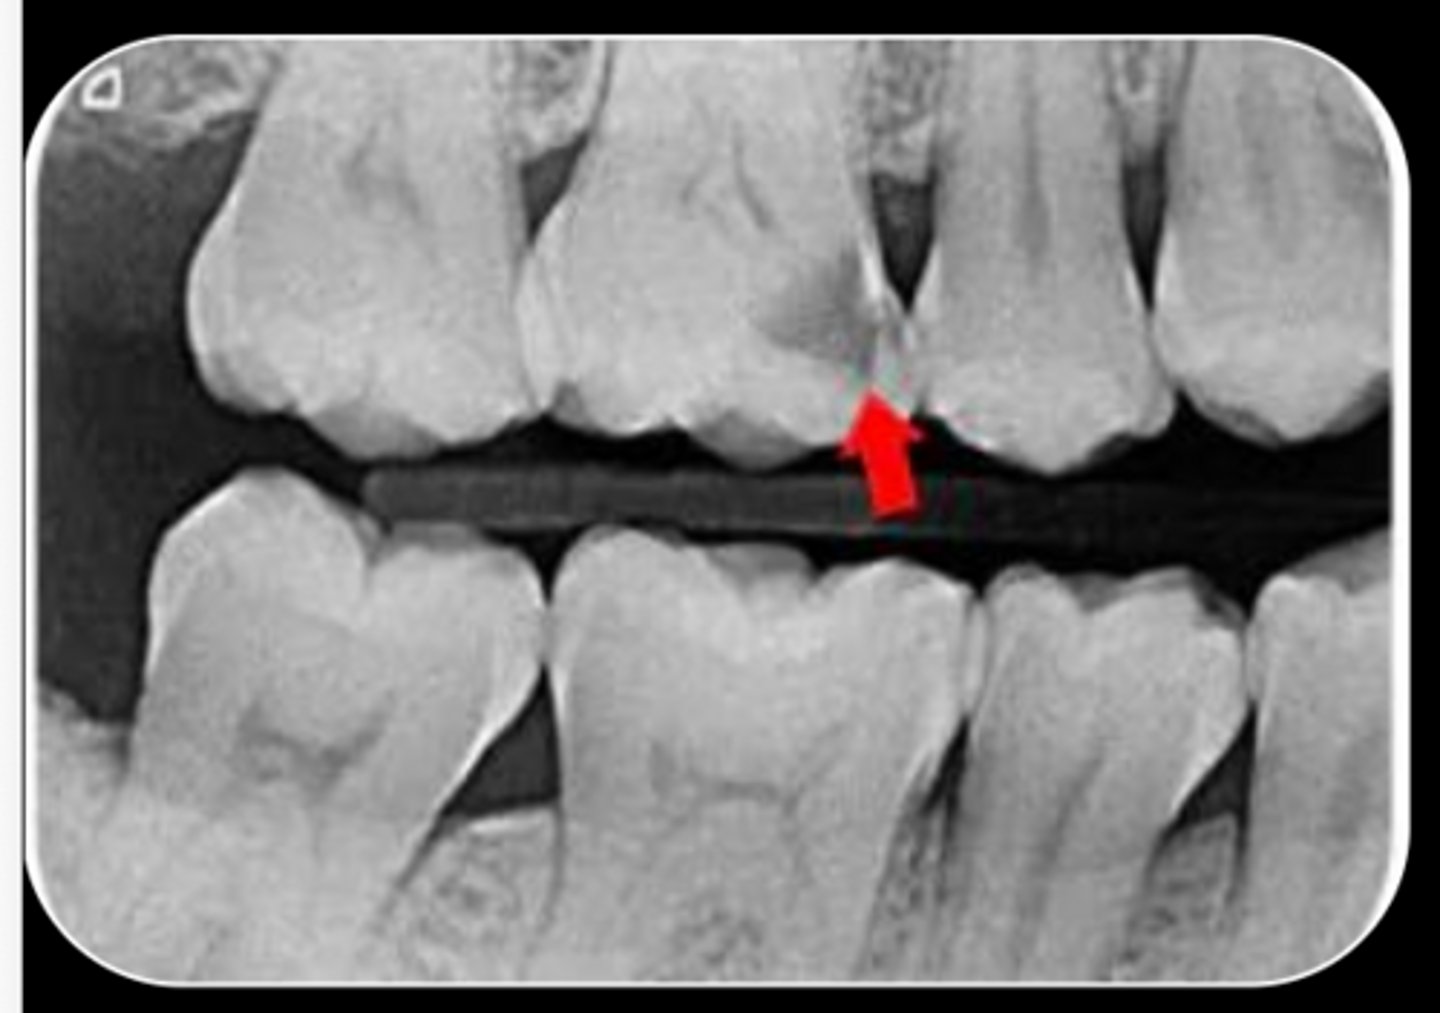

Is this foreign object lingual or buccal to the teeth?

buccal

A 35-year-old patient presents with spontaneous pain in the maxillary first molar. The pulpal diagnosis is symptomatic irreversible pulpitis and periapical diagnosis of symptomatic apical periodontitis, and nonsurgical root canal therapy is initiated.

During access preparation, the clinician identifies the mesiobuccal canal but suspects an additional

canal in the same root.

Two periapical radiographs are obtained:

- The first radiograph is taken with normal horizontal angulation.

- The second radiograph is taken with a distal horizontal tube shift.

On the second image, the suspected canal appears to move distally, in the same direction as the tube shift.

Based on these findings, where is the suspected canal most likely located?

A. Buccal to the main mesiobuccal canal

B. Lingual (palatal) to the main mesiobuccal canal

C. Apical to the main canal

D. Distal to the main canal